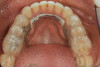

(3.) Preoperative occlusal view of lower arch with orthotic in place.

Figure 3

Ultimately, the patient developed joint and muscle symptoms due to his lack of posterior support and sought the help of a specialist. His bite was analyzed, and he was fitted with a dental orthotic that allowed his teeth to touch in centric relation (Figure 3). This was intended to be a temporary measure to stabilize the patient's bite and make him comfortable, but before any permanent treatment could be carried out, he moved abroad and had been living with the device for more than four years before the time of the consultation. He stated that his bite was now very stable with the orthotic, but he was looking for a more permanent solution and also wanted to improve the overall appearance of his smile.

A comprehensive examination was carried out, and preoperative photographs were taken (Figure 1 through Figure 4). The patient presented with fair oral hygiene and slight, generalized tissue inflammation. Caries and defective restorations were detected on teeth Nos. 4, 5, 13, and 14. The crown on tooth No. 12 was showing signs of leakage, and although the endodontic access cavity had been temporarily restored with composite, this endodontic re-treatment was acceptable and the tooth was otherwise symptom-free. Erosion was present on most of the posterior teeth and the cuspids, and abrasion was noted on teeth Nos. 4, 5, 10, 11, 20, 21, 22, 28, and 29. An examination of the patient's muscles, joints, and bite revealed no joint sounds, a normal range of motion, and negative joint load and immobilization tests.

The patient's removable dental orthotic covered the lower bicuspids and first molars. With the orthotic in place, there was shim stock contact on all posterior teeth and on the second molars that were not covered by the appliance. However, there was no incisal overlap and a lack of anterior guidance.11 When the orthotic was removed, solid shim stock contacts were present on the second molars and the right lateral incisor. These contacts were reproduced every time the appliance was removed. The same contacts were found on the patient's mounted models, which confirmed that the joints were in centric relation. Whether the lower second molars had overerupted as a result of wearing the appliance or had already been in this position before the orthotic was fitted could not be established. Apart from these three contacts, no other teeth touched, and there was a 2-mm space between the posterior teeth, making mastication difficult. Interestingly, wear facets were present on the palatal surfaces of the upper central and lateral incisors, indicating that at some point in time, there had been significant overlap of the anterior teeth and a possible constriction of the chewing envelope. Analysis of a cephalometric radiograph showed a class II growth tendency with a reduced mandibular plane angle, which supported the theory that the patient had at one time possessed a class II occlusion.